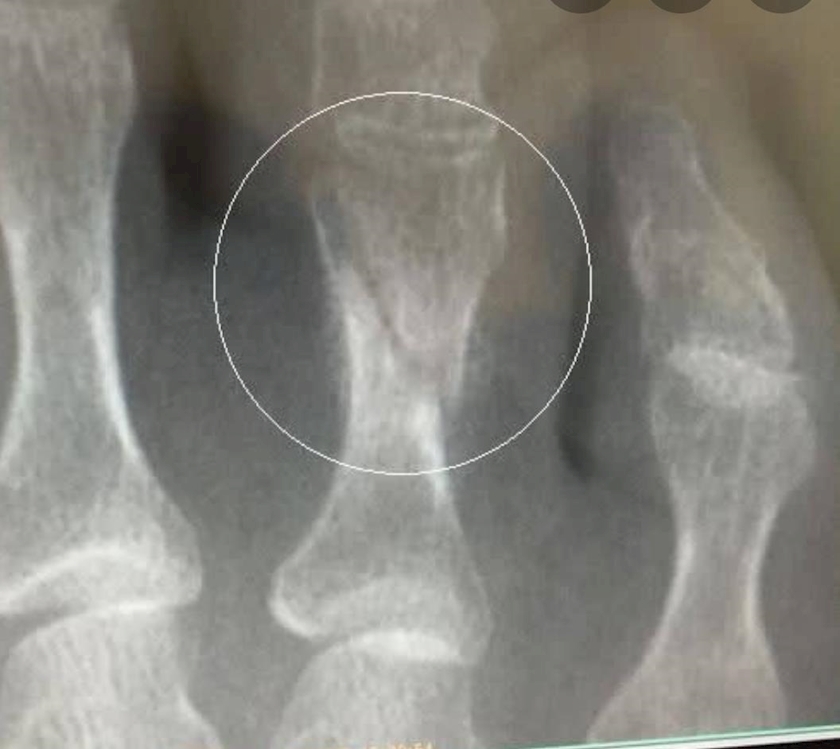

2週間ぶりのレントゲン

前とあまり変わってない

⬆参考画像

(今まさにこんな感じ

)

超音波治療をすることに

コレを続けると

骨の形成期間が4割早まるんだって